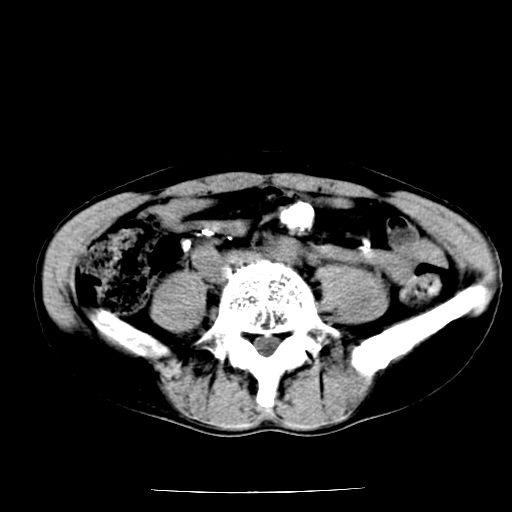

男,59岁,“结核性胸膜炎”30余年,胸部经常疼痛,多次x检查提示“肺部”炎症。腹部疼痛5日,b超提示:“肝内短管结石,余显示不清,建议进一步检查。”

两肺结核并右侧胸腔积液;脾脏、腹腔及腹膜后淋巴结结核[陈旧性];肝内胆管结石

胸部腹部都是结核(双肺。纵隔淋巴结,肝脏,脾脏,肠系膜)